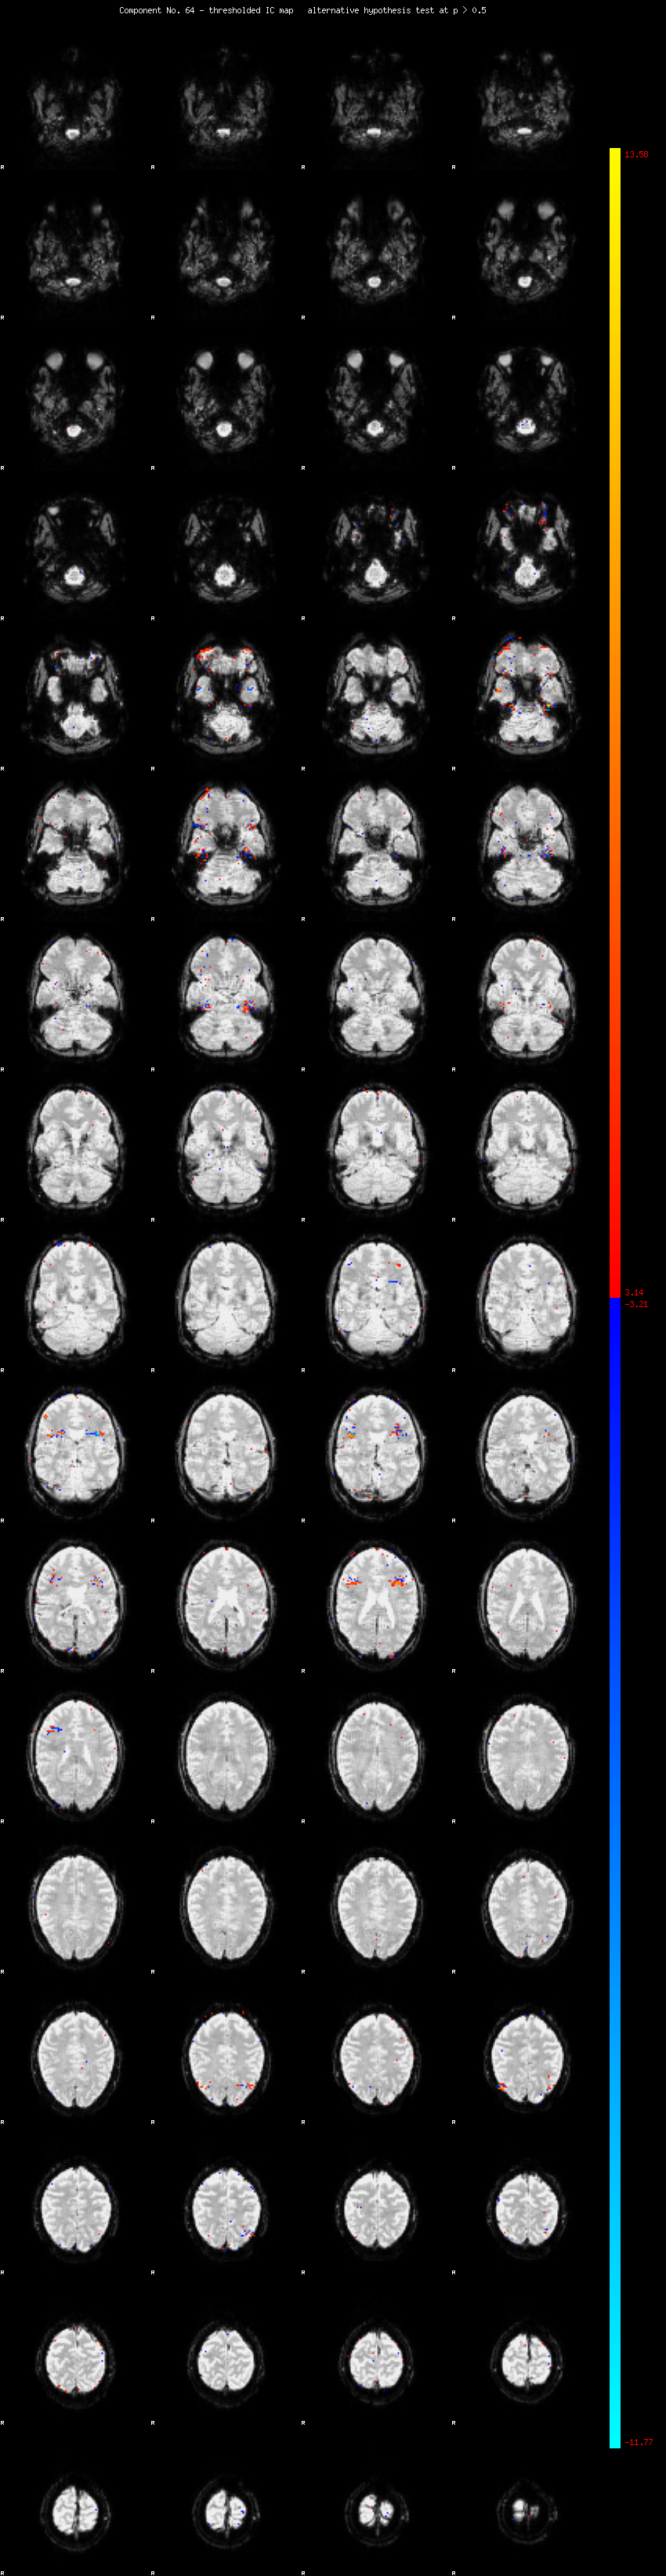

MELODIC Component 64

0.84 % of explained variance;     0.56 % of total variance

MMfit